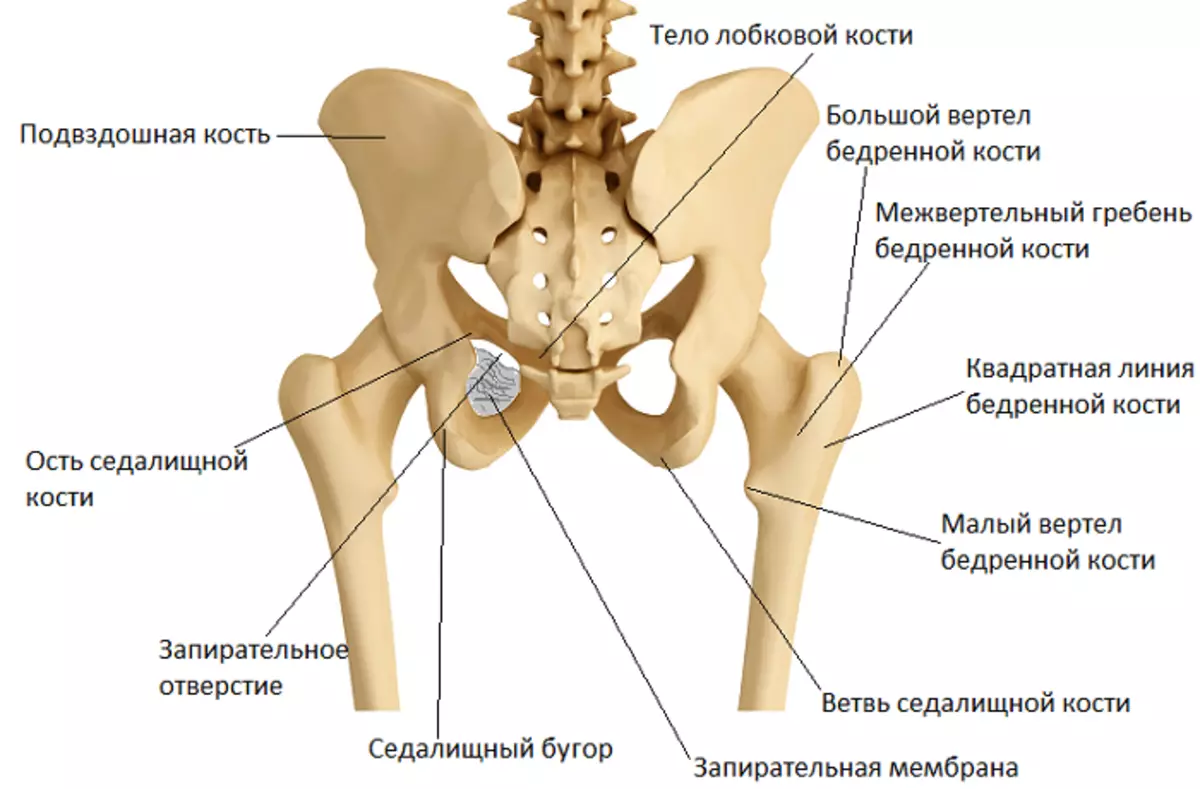

Боль в малом тазу у женщин: Причины и подходы к лечению